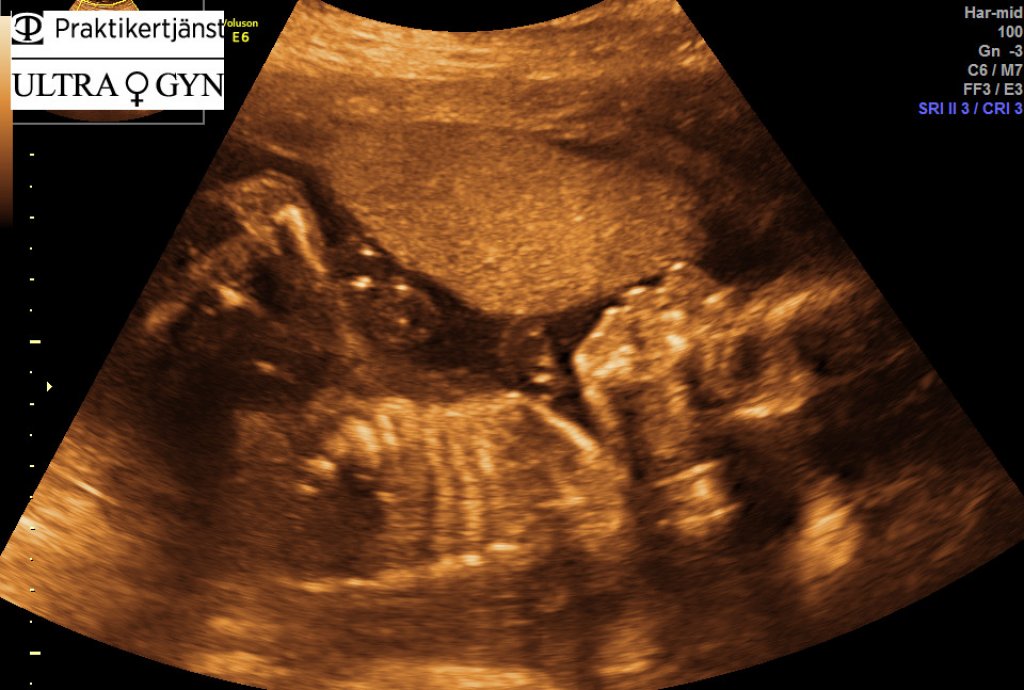

Efter ett par minuter sa läkarna att bebisen var på väg ut och strax därefter så började vår lillstrumpa att skrika.

De tog med sig Kenny in i ett angränsande rum för att torka av henne och kontrollera att allt var bra innan de kom och la henne vid mig så jag fick pussa och gosa på henne. Vilken lycka!